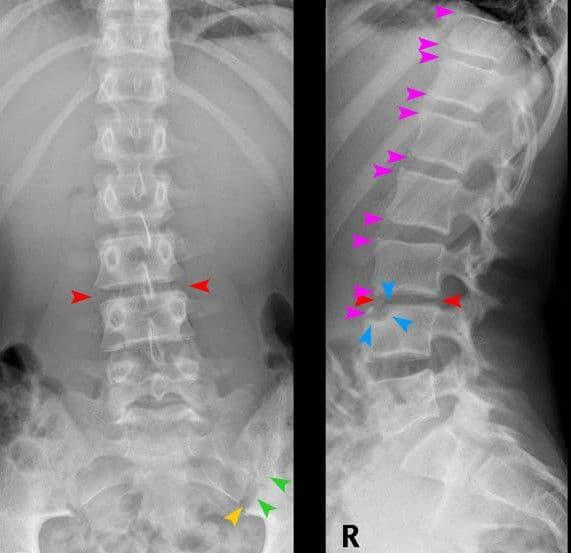

Marshall Deltoff DC, DACBR, FCCR(C) graduated with honors from the Canadian Memorial Chiropractic College in Toronto. He has over 30 years of academic, clinical and regulatory experience, having performed and read over 140,000 plain film x-ray examinations. He is the co-author of The Portable Skeletal X-Ray Library, a textbook of radiological bone diseases, as well as several book chapters, manuscripts and research papers and was selected to assist Yochum, T. & Rowe, L. in the final editorial process of textbook: “Essentials of Skeletal Radiology”. Dr. Deltoff has served as the President of the College of Chiropractors of Ontario, the regulatory body for over 5,000 DCs in that province. Currently, he is Professor of Radiology at Barcelona College of Chiropractic, and manages Images Radiology Consultants, an online x-ray reporting service for colleagues worldwide.